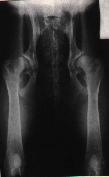

Na levém snímku můžeme vidět kyčelní klouby zdravého

zvířete, ale na druhém snímku je zrentgenované zvíře postižené těžkou

dysplazií.

Stupeň 4 / E / těžká:

- výrazná anatomická nepravidelnost

- zřetelná luxace a oddálení kloubních ploch, koxatróza,

deformace hlavice

- oploštění předního okraje acetabula s tvorbou

osteofytů

- Norbergův úhel je pod 90°